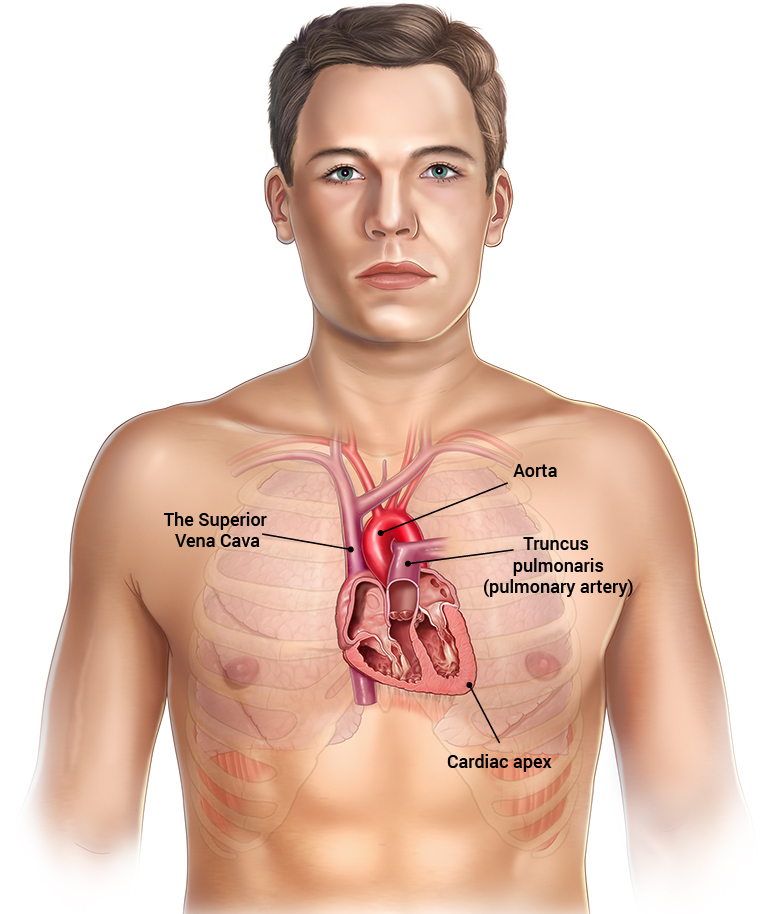

Изображения и визуализация внутренних органов человека